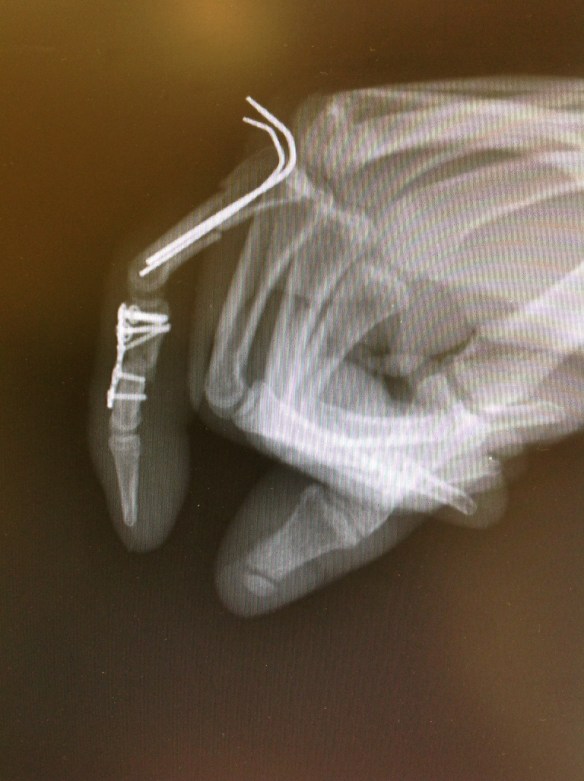

Se procedió a síntesis anterógrada de la F1 con 2 agujas de Kirshner introducidas con la articulación metacarpofalángica en flexión máxima para no limitar la rehabilitación precoz.no coloqué placa de síntesis pues tengo comprobado que en la F1 las placas dan lugar a gran número de rigideces que obligan a su retarda y a tenolisis. En la F2 conminuta procedí a colocar placa con injerto de radio, en lidera rotación radial para facilitar la pinza término-terminal de un índice que por la lesión del aparato extensor asociada ya se preveía que tendría poca mobilidad de IFD. Se inició kinesiterapia activa autoasistida a los 3días postop.

Se retiraron las agujas tras consolidación de la F1.

Este es el estado actual a las 9 semanas postoperatorias.